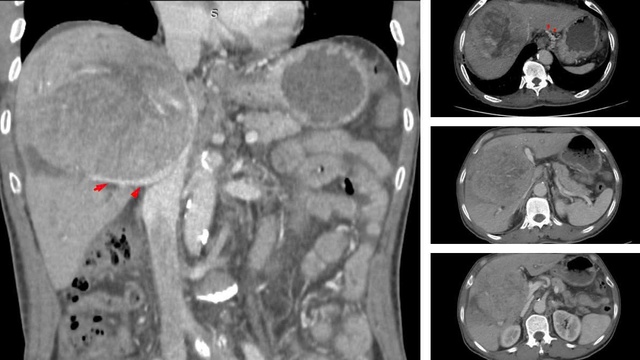

Hình ảnh khối u gan giai đoạn muộn. Ảnh: BVCC

BSCKII Nguyễn Trường Giang, Phó Giám đốc Trung tâm cho biết: "Khối u khổng lồ chiếm gần hết nhu mô gan, chèn ép rốn gan và tĩnh mạch, khiến bệnh nhân bị phù chân và cổ chướng".